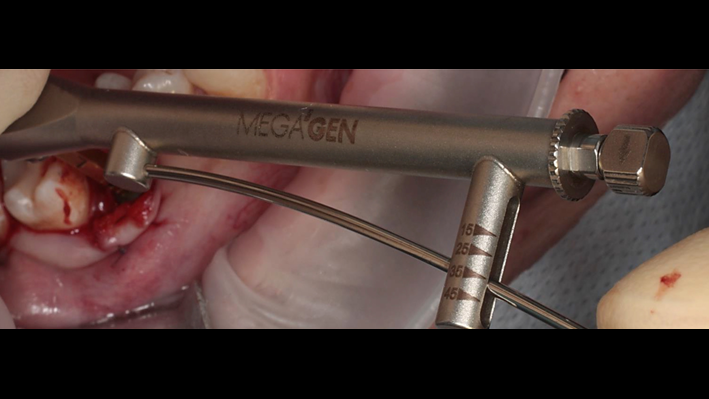

Clinical case: Ridge splitting technique using SmarThor + AnyRidge as expander

- Courtesy of Dr.Kwang-Bum Park, Korea -

Keywords

AnyRidge, ridge splitting, GBR, Dr. Kwang-Bum Park, mandibular posterior, SmartThor, Mega-Oss, thin ridge, bone regeneration

Products:

AnyRidge implant system. SmarThor, Mega-Oss